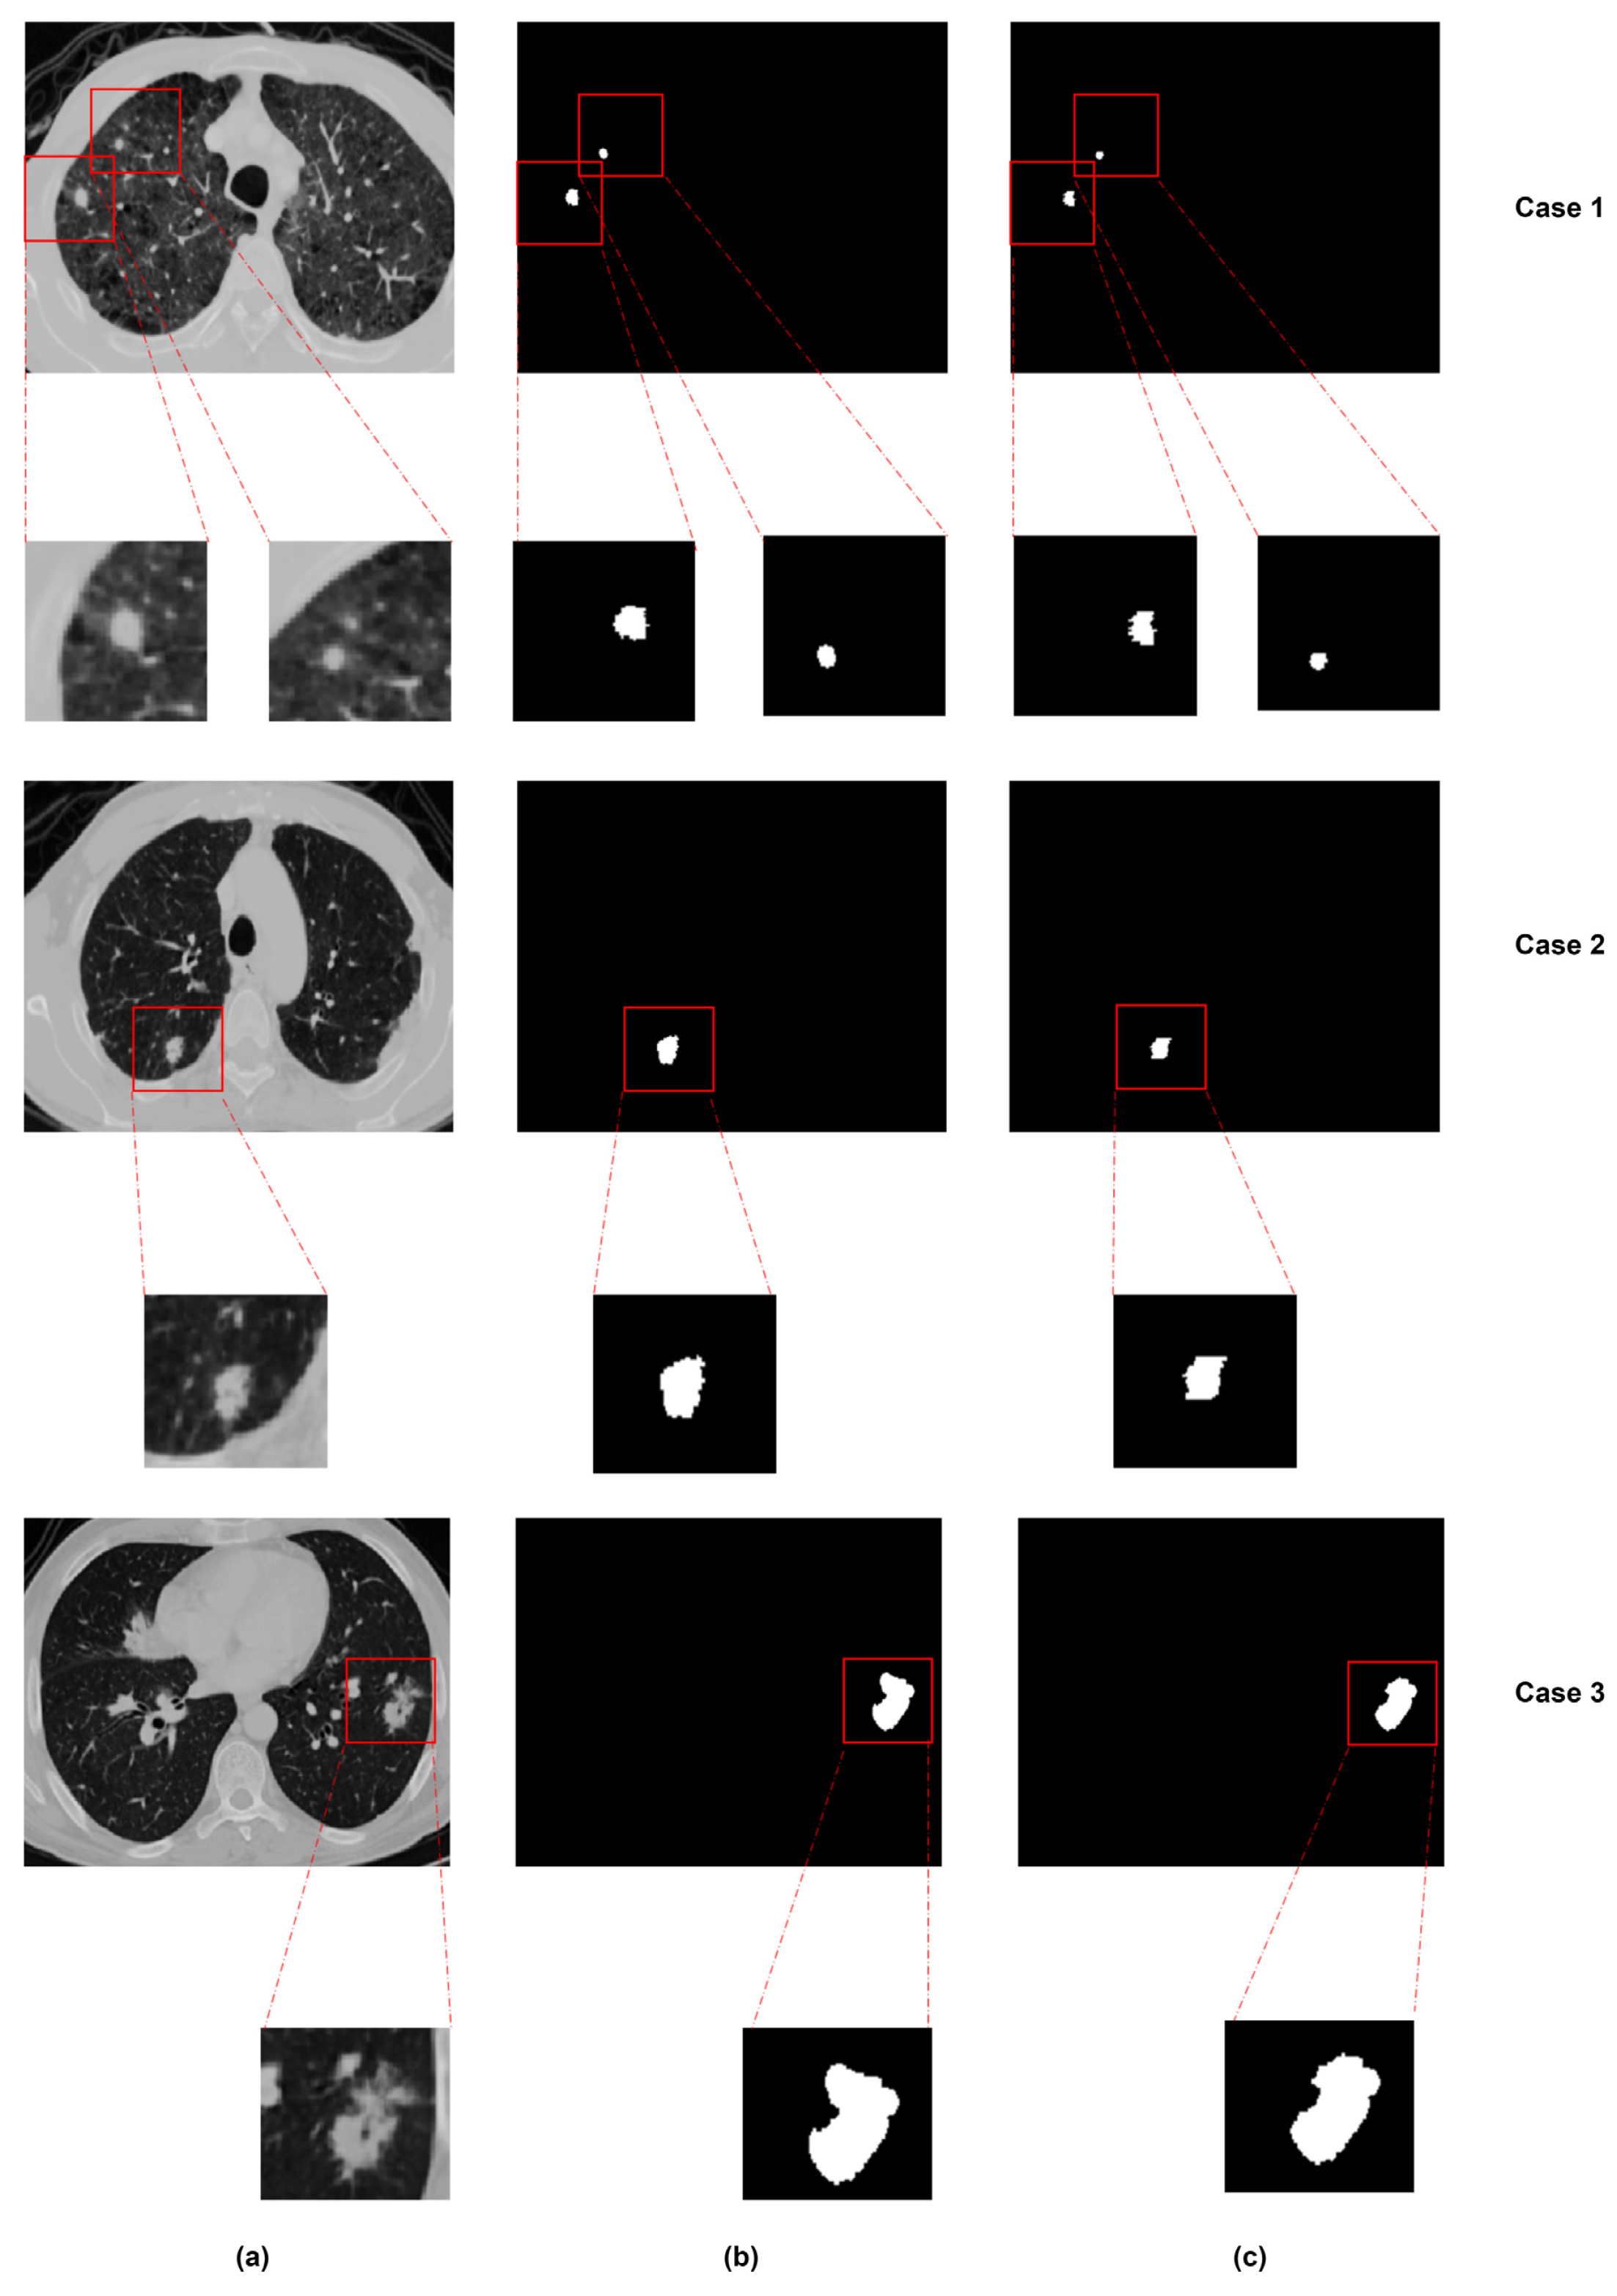

7. Lung Nodule Segmentation

7.1. Traditional Methods

7.2. Deep Learning-Based Segmentation